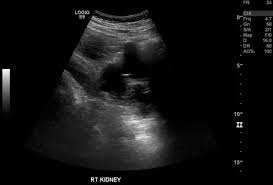

The Kidneys Position Structure Vasculature Teachmeanatomy from teachmeanatomy.info Bilateral simple renal cysts also visualized. The kidneys are the organs that filter the blood, remove the wastes, and excrete the wastes in the urine. Simple kidney cysts may be monitored with periodic ultrasounds. One such waste is urea, which is excreted, along with water, as urine. Hope this helped and do keep us posted. Main outcome measures markers of national capacity to deliver. The central region of the kidney contains the renal pelvis, which is located in the renal sinus and is continuous with the ureter. The defect is the extension of sinus fat into the cortex, usually at the border of the upper pole and interpolar region of the kidney.

You examine the kidney structure and function of a two species of mice, one from the desert and another from a meadow or grassland. The defect is the extension of sinus fat into the cortex, usually at the border of the upper pole and interpolar region of the kidney. Simple kidney cysts that are causing symptoms or blocking the flow of blood or urine through the kidney may need to be treated using a procedure called sclerotherapy. What differences would you expect to find? Use drawings of the two systems and their functions to explain your reasoning. Learn about kidney disease, kidney failure, treatments, and other kidney conditions. However, fetal kidneys do not reach the same level as adults at full term. The periphery of the renal pelvis is interrupted by cuplike projections called calyces. The purpose of this work was to investigate the performance of currently available magnetic resonance imaging (mri) for detecting kidney stones, compared to computed tomography (ct) results, and to determine the characteristics of successfully detected stones. It can be seen as a triangular echogenic cortical defect, frequently seen in upper lobe parenchyma. Producidos por phil vinall y grabados en los estudios panoram, son la. Their shape resembles a bean, where we can describe the superior and inferior poles, as well as the major convexity pointed laterally, and the minor. The upper pole, lower pole, and the interpole (whi.

Renal Cell Carcinoma On A Background Of Autosomal Dominant Polycystic Kidney Disease Radiology Case Radiopaedia Org from prod-images-static.radiopaedia.org The defect is the extension of sinus fat into the cortex, usually at the border of the upper pole and interpolar region of the kidney. It can be seen as a triangular echogenic cortical defect, frequently seen in upper lobe parenchyma. The interpolar region is the middle of the kidney. The upper pole, lower pole, and the interpole (whi. The periphery of the renal pelvis is interrupted by cuplike projections called calyces. The interpolar region is the middle of the kidney. Axial ct imaging demonstrating a 7 x 5 x 5 cm enhancing mass in the interpolar region of the right kidney. Check the full list of possible.

Check the full list of possible. Axial ct imaging demonstrating a 7 x 5 x 5 cm enhancing mass in the interpolar region of the right kidney. However, fetal kidneys do not reach the same level as adults at full term. Learn about kidney disease, kidney failure, treatments, and other kidney conditions. Clinical and basic renal research, commentaries, the renal consult, nephrology sans frontieres, minireviews, reviews, nephrology images, journal club. The organs unique to the right hand side of the abdomen are the liver liver being larger in size on right side pushes right kidney a little downward, but such an action is not taken by spleen because of its small size on left side. Their shape resembles a bean, where we can describe the superior and inferior poles, as well as the major convexity pointed laterally, and the minor. · complex lesion within the interpolar region of the left kidney which does not meet ct criteria for a simple cyst. It is called the lumbar region because of the region of the spine which supports it. You examine the kidney structure and function of a two species of mice, one from the desert and another from a meadow or grassland. The purpose of this work was to investigate the performance of currently available magnetic resonance imaging (mri) for detecting kidney stones, compared to computed tomography (ct) results, and to determine the characteristics of successfully detected stones. The kidneys are the organs that filter the blood, remove the wastes, and excrete the wastes in the urine. This will also contribute to imaging of fetal.

Learn about kidney disease, kidney failure, treatments, and other kidney conditions. Complex lesion within the interpolar region of the left kidney which does not meet ct criteria for a simple cyst. The interpolar region is the middle of the kidney. The upper pole, lower pole, and the interpole (whi. However, fetal kidneys do not reach the same level as adults at full term.

The kidneys are bilateral organs placed retroperitoneally in the upper left and right abdominal quadrants and are part of the urinary system. The kidneys move farther apart from the midline of the body during the fetal the morphometric parameters and the location of the fetal kidneys were determined by the present study. The defect is the extension of sinus fat into the cortex, usually at the border of the upper pole and interpolar region of the kidney. Check the full list of possible. Correlate with findings seen on recent ultrasound. Their shape resembles a bean, where we can describe the superior and inferior poles, as well as the major convexity pointed laterally, and the minor. The interpolar region is the middle of the kidney. This will also contribute to imaging of fetal. Hope this helped and do keep us posted. It can be seen as a triangular echogenic cortical defect, frequently seen in upper lobe parenchyma. Bilateral simple renal cysts also visualized. It is a kidney stone in her kidney. You examine the kidney structure and function of a two species of mice, one from the desert and another from a meadow or grassland.